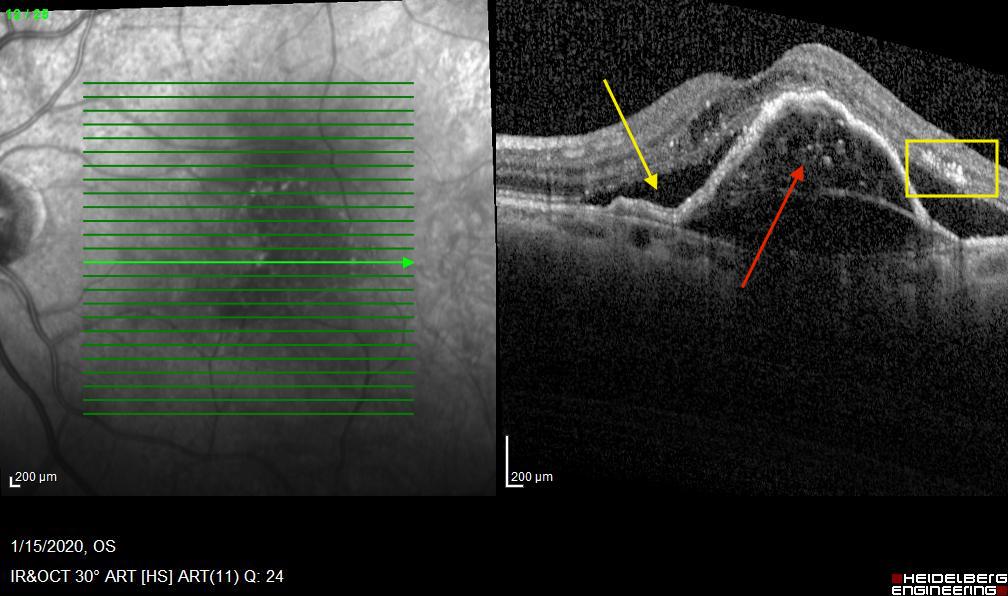

The ensemble of image techniques cover different perspectives and retina biomarkers (Table I). Color fundus photography reveals hemorrhages (Figure 1 left). Fluorescein angiography (FA) reveals speckled hyperfluorescence (Figure 1 center), while OCTA sees the neovascular membrane as a hyperfluorescent neovascular network (Figure 1 right). The corresponding OCT scan for Figure 1) better shows biomarkers like elevation of the retinal pigment epithelium, subretinal fluid or hard exudates (Figure 2).

We illustrate here how the processing steps lead to the binary image, which contains essential information about the blood vessels. Fig. 9 shows the steps involved in the Data Cleaning phase and Otsu Thresholding.

Fig. 10 presents the image processing techniques and their outcomes at each iteration. The grayscale images progressively approach a binary representation, as seen after the application of multiple binarization techniques. The salt and pepper filter removes part of the noise. In the final image, all components are colored in a way that highlights the principal component. Any remaining noise is removed in Fig. 11, which also shows the result after applying region filling techniques.

To assess the performance, we used the Jaccard Distance = and the Dice coefficient to compare the two sets of data in our scenario: the 1st batch and the 3rd one. A Jaccard Index is 0.8912, suggesting that 89.12% of the pixels identified during the Data Cleaning and Image processing module were also identified by the ophthalmologist. The Dice Coefficient ranges from 0 to 1, where 0 indicates no overlap, and 1 indicates complete overlap (identical sets). The value of the Dice coef = 0.92 is very high, which suggests that the two sets A and B have a large overlap.

The pictures represent the right eye of a patent suffering from nAMD. The first image - (a) from Fig. 12 - was taken on June 27th 2023 and the second one - (c) from Fig. 12 - was taken almost a year later, on June 11th 2024.